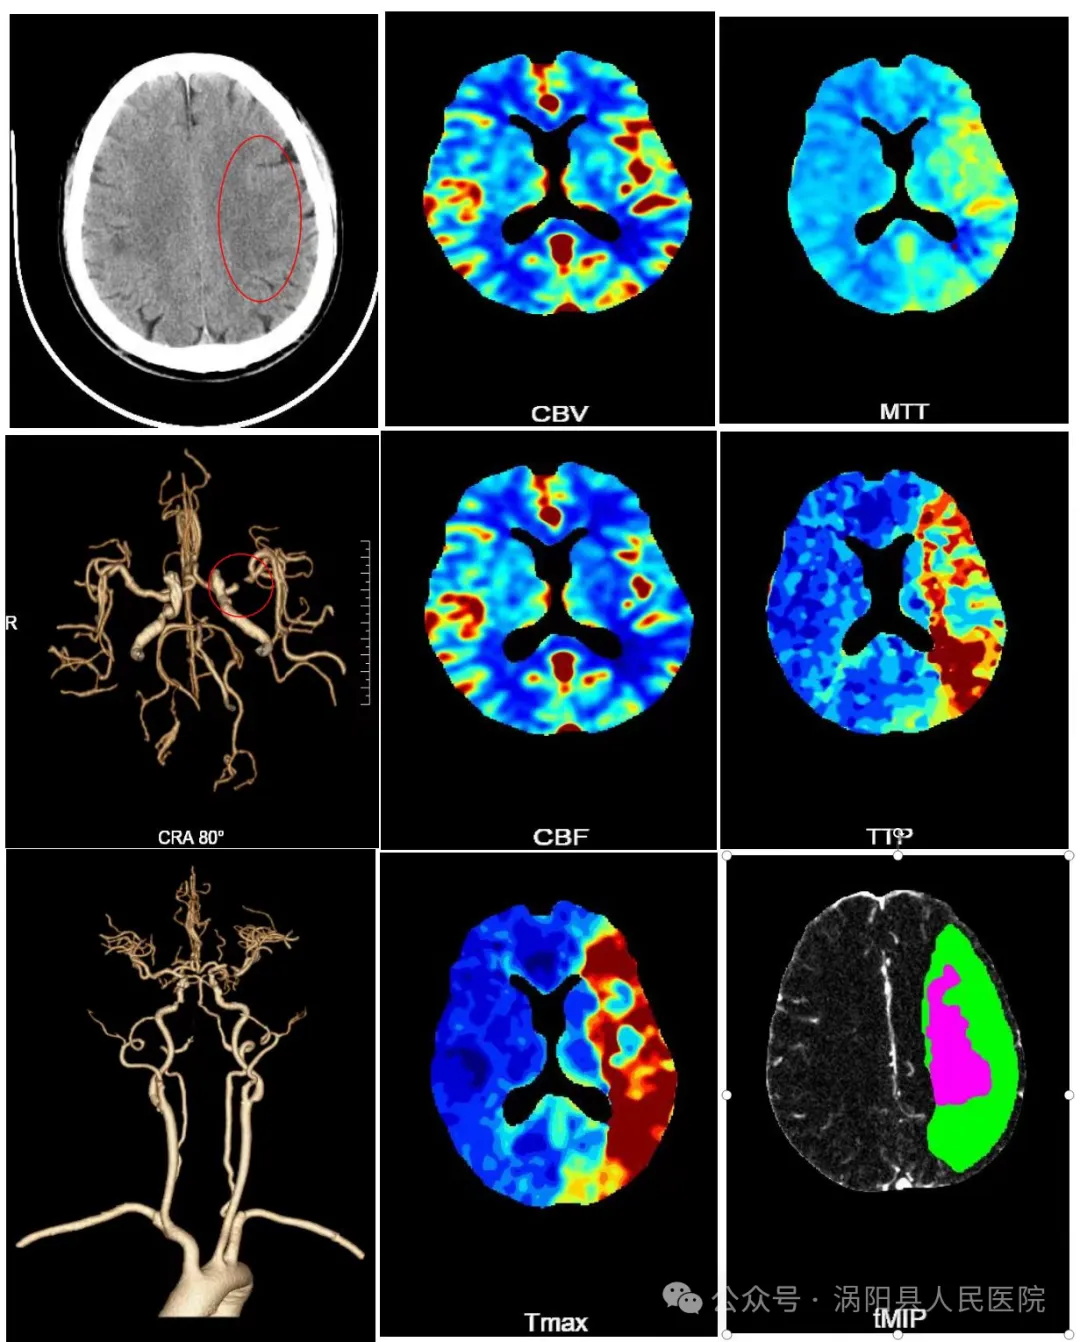

无限制一站式脑卒中成像是一次造影剂注射、一次扫描,同时完成颅脑CT平扫、头颈CTA、颅脑多期增强和全脑CTP灌注成像,极大增加了对脑卒中的快速诊断,加快救治流程,为患者的救治争取更多的时间。